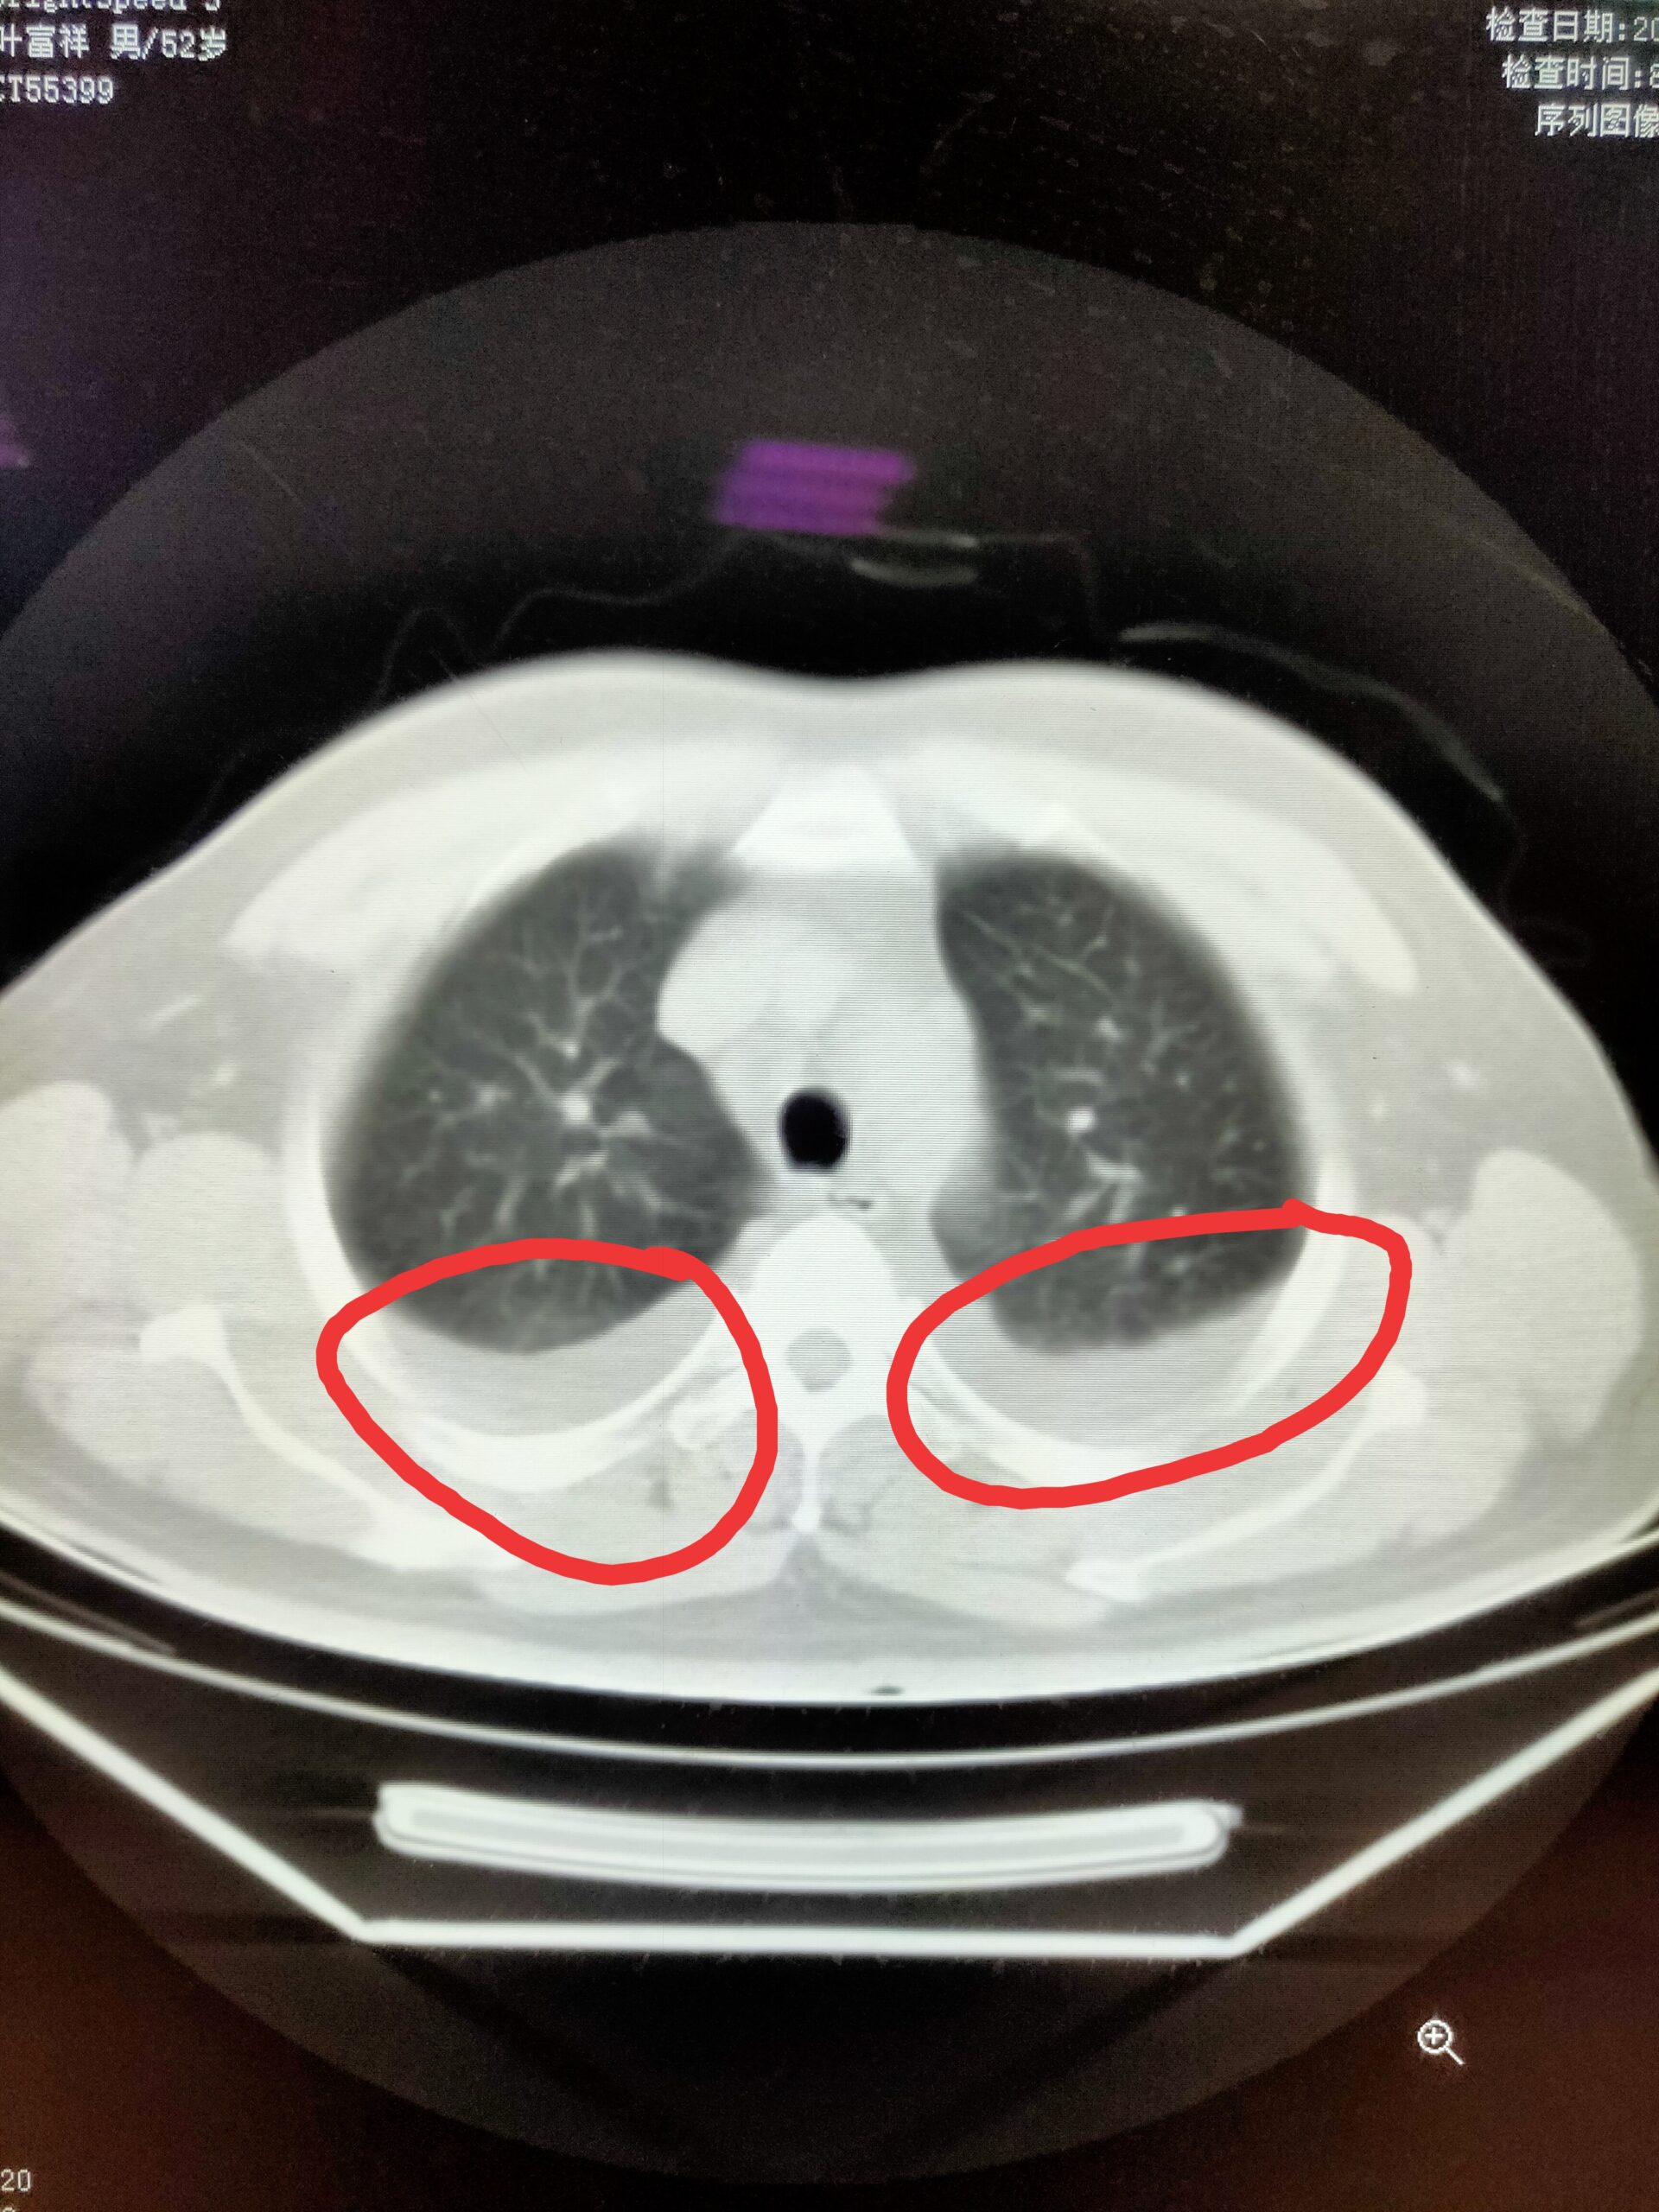

胸腔积液CT图